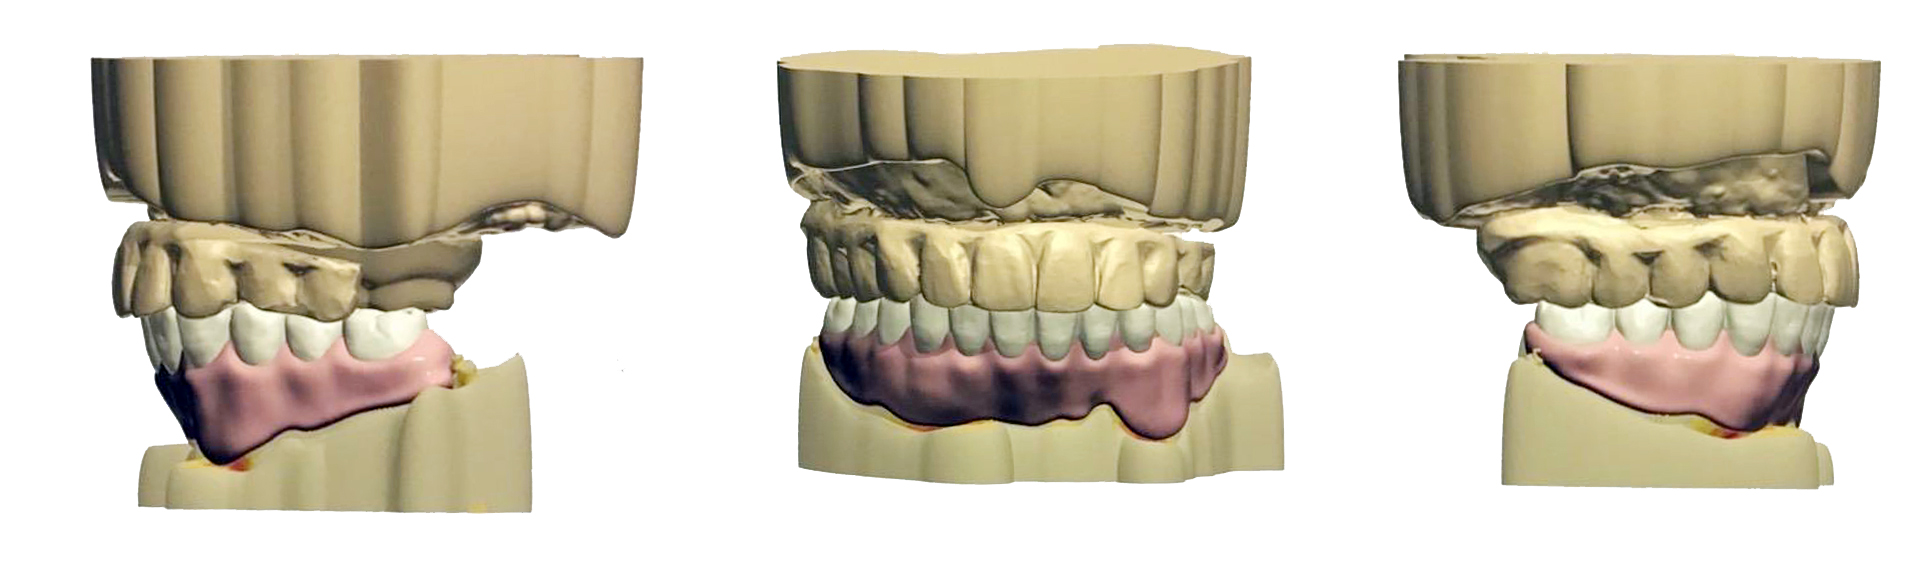

數位排牙在全口重建複雜的案例中,若只有嘴巴言語、文字敘述,無法直觀的說明牙齒治療後的狀況,現在有了數位排牙的輔助,可以利用3D立體的方式,讓患者了解未來牙齒的位置與型態,是醫師和患者之前很棒的溝通橋樑。

當今全口重建治療中,All-on-4 技術為缺牙患者帶來嶄新希望,而臨時假牙在療程過渡期扮演著極其重要的角色,透過當日完成的臨時假牙,患者能即刻恢復基本咬合功能,不僅大幅提升生活品質,也為後續正式假牙的製作打下良好基礎。

在轉換至正式假牙階段,假牙醫師會從多個層面觀察並細緻調整最終假牙的型態,隨著數位印模與3D模型技術的導入,醫師和牙技師能在電腦上精確規劃每一顆 All-on-4 牙齒的位置與角度,結合臉部掃描或外觀照片,更能模擬未來裝戴效果。

數位化流程讓假牙製作過程更加靈活且精準,只要有數位檔案,即可完整複製臨時假牙的優點,並進行細微的調整,減少傳統手工排列可能產生的人為誤差,此外,數位排牙能以3D立體模式預先呈現治療成果,讓患者直觀了解未來牙齒的樣貌,成為醫師與患者溝通的重要橋樑,不僅提升治療精度,也讓追求完美笑容成為可能。